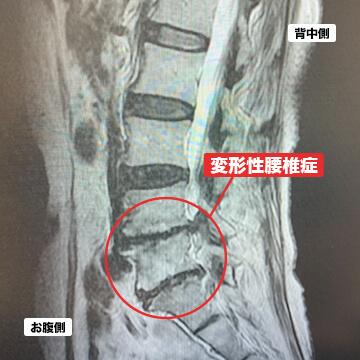

- 変形性腰椎症

変形性腰椎症とは、腰骨の加齢変化で骨棘(こつきょく)と呼ばれる骨の棘や背骨の変形が生じることを言います。骨棘や背骨の変形が進むと、神経を圧迫する脊柱管狭窄症も併発することがあります。主に腰の鈍痛、だるさ等が症状として現れます。